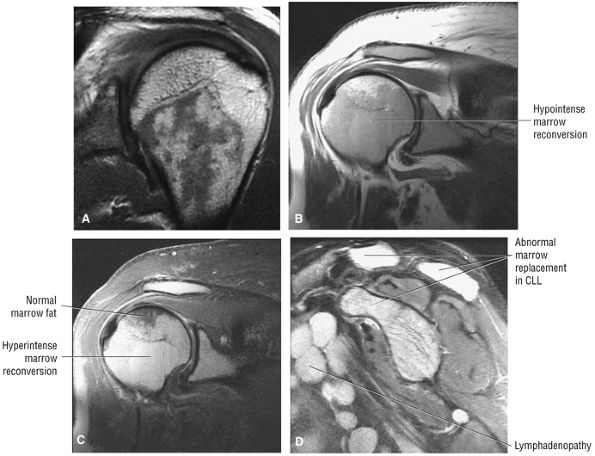

FIGURE 8.10 ● (A) Coronal PD FSE image showing normal hypointense red marrow signal distal to the proximal humeral physeal scar. Red marrow may partially exist in subchondral locations of the proximal humeral epiphysis, providing characteristic T1 and T2 signal intensities. (B, C) Marrow reconversion in polycythemia vera, a myeloproliferative disorder. Red marrow signal intensity is apparent proximal to the physeal scar. Red marrow demonstrates lower signal intensity than fat on coronal PD-weighted images (B) and is hyperintense relative to fat signal on coronal FS PD FSE images. (C). Red marrow associated with pathologic conditions tends to image with greater hyperintensity than normal areas of persistent red marrow. (D) Abnormal hyperintense marrow replacement in chronic lymphocytic leukemia (CLL) on a sagittal FS PD FSE image. CLL is not associated with high-dose radiation or benzene exposure.